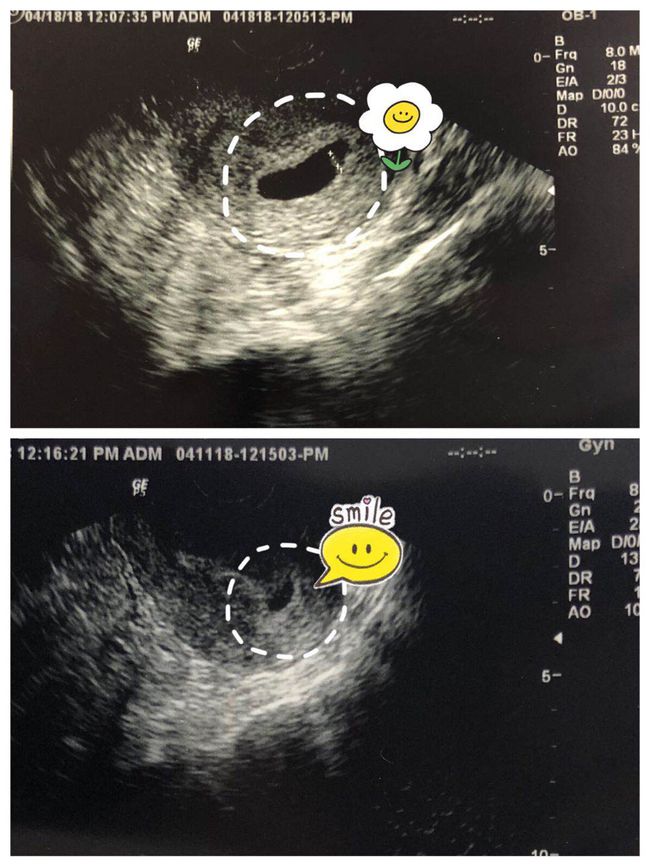

3. 诊断妊娠相关疾病:如先兆流产、宫外孕等,孕酮检测可以帮助医生做出诊断。